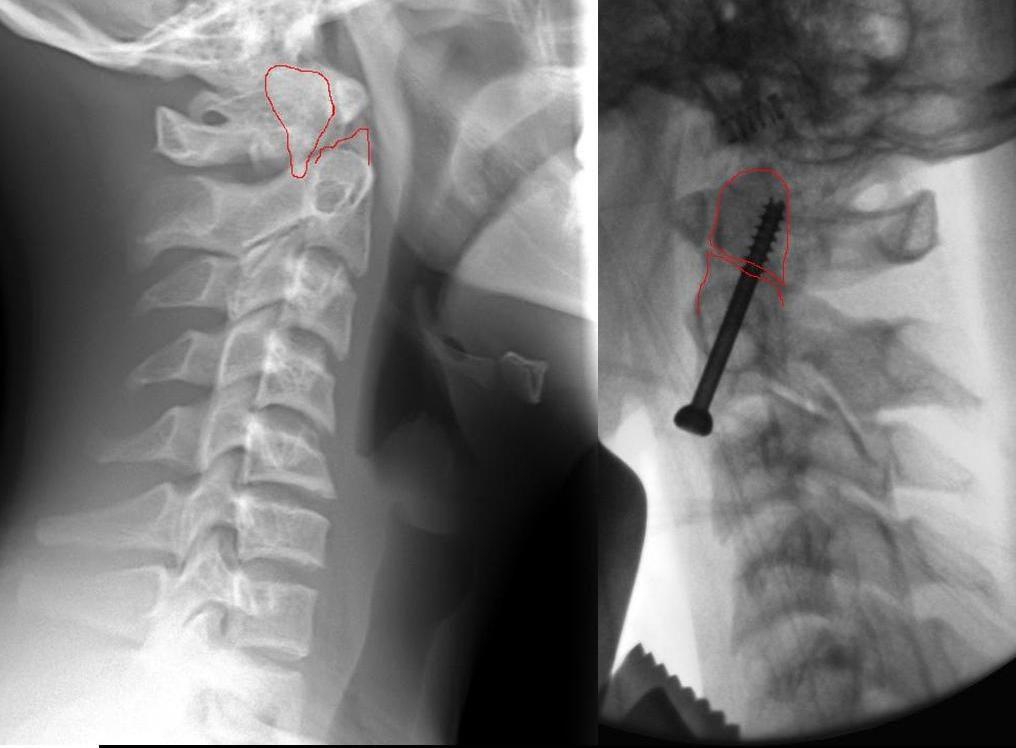

הנער, שהגיע לפני כשבוע לחדר המיון עם חבלה חמורה בעמוד השדרה הצווארי, סבל משבר בלתי יציב בחוליה הצווארית השנייה, חבלה המוכרת יותר בשם "שבר במפרקת". חבלה כזו יכולה לגרום למוות כמעט וודאי, במקרה והשבר פוגע בחוט השדרה.

למזלו של הנער, הפגיעה נגרמה בחוליה מסוימת, שאפשרה לרופאים להציל את חייו, אבל גם לספק לו איכות חיים גבוהה בהמשך, זאת הודות לניתוח חדשני שכמוהו בוצעו בודדים בארץ, ונעשה לראשונה בצפון, במהלכו בוצע קיבוע לשבר, באמצעות בורג בודד בלבד.

על רקע סוג הפציעה וגילו של המטופל החליטו הרופאים לבחור בדרך לא שגרתית לטיפול ולקבע את השבר באמצעות בורג בודד בלבד מאזור בסיס הצוואר, מקדימה מעל עצם הבריח, ולהימנע כליל מפגיעה בוושט, בעורקים או בקנה הנשימה.

גישת הטיפול בנער הפצוע סייעה לרופאים להבטיח את קיבוע השבר המסוים בחוליה C2 באופן מידי, כאשר באופן זה, הסיכויים לחיבור העצם הינם הגבוהים ביותר. אולם החלק המהותי ביותר בניתוח הוא שטווח התנועות הסיבוביות של הצוואר נשאר כמו שהיה וביכולת הנער לבצע תנועות סיבוביות, תוך פחות מ-48 שעות מהניתוח.

את הניתוח ביצעו ד"ר אליאס חדאד, מנתח בכיר ביחידת עמוד שדרה ברמב"ם וד"ר עמית קרן, רופא בכיר במערך האורתופדי, בהנחיית ד"ר חנני עמוס, מנהל יחידת עמוד השדרה בביה"ח. בבדיקות ה-CT שבוצעו לאחר הניתוח, נמצא שהשבר שוחזר וקובע באופן משביע רצון, והנער שוחרר לביתו, כשהוא אינו סובל מכאבים משמעותיים.

"בניתוח שביצענו בנער החתך הניתוחי שנשאר הינו קטן, אין קדיחות בגולגולתו ואין ברגים מיותרים", מסביר ד"ר חדאד. "כדי לוודא שהכיוון והקיבוע של אותו שבר מתבצע בצורה האופטימאלית בוצע שיקוף באמצעות שני מכשירי דימות, כשהתוצאה שקיבלנו הייתה חייבת להיות מדויקת ביותר. ברגע שקיבלנו את התמונה המלאה, החלטנו לפעול בשיטת הקיבוע השלישית, שלמרות מורכבותה הטכנית, היתרונות שלה לרווחת המטופל בהמשך חייו, הינם הגבוהים ביותר".